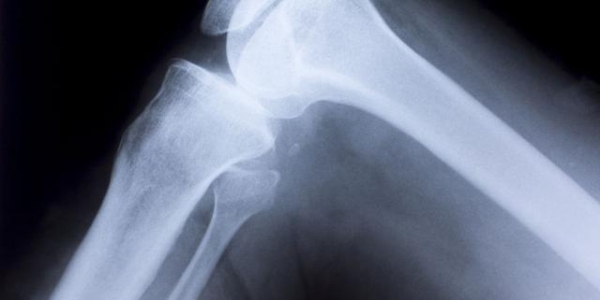

水里走最香,浮力卸掉六成体重,膝盖秒减压。

每三个月给膝盖做个超声,比拍全家福还重要。